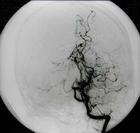

脑血管造影可以发现颈内动脉起始部、大脑前、中动脉起始段狭窄或不显影,基底节区可见大量细小血管团如吸烟吐出的烟雾。此外可见脑内形成侧支循环代偿支。随着病程的延长,代偿吻合支的数量逐渐减少或缩小。

5.脑血管造影 见颈内动脉虹吸上段和大脑前、中动脉起始部狭窄,脑底烟雾状异常血管网和广泛的侧支循环形成。应与脑动脉硬化性脑梗死和动静脉畸形鉴别。